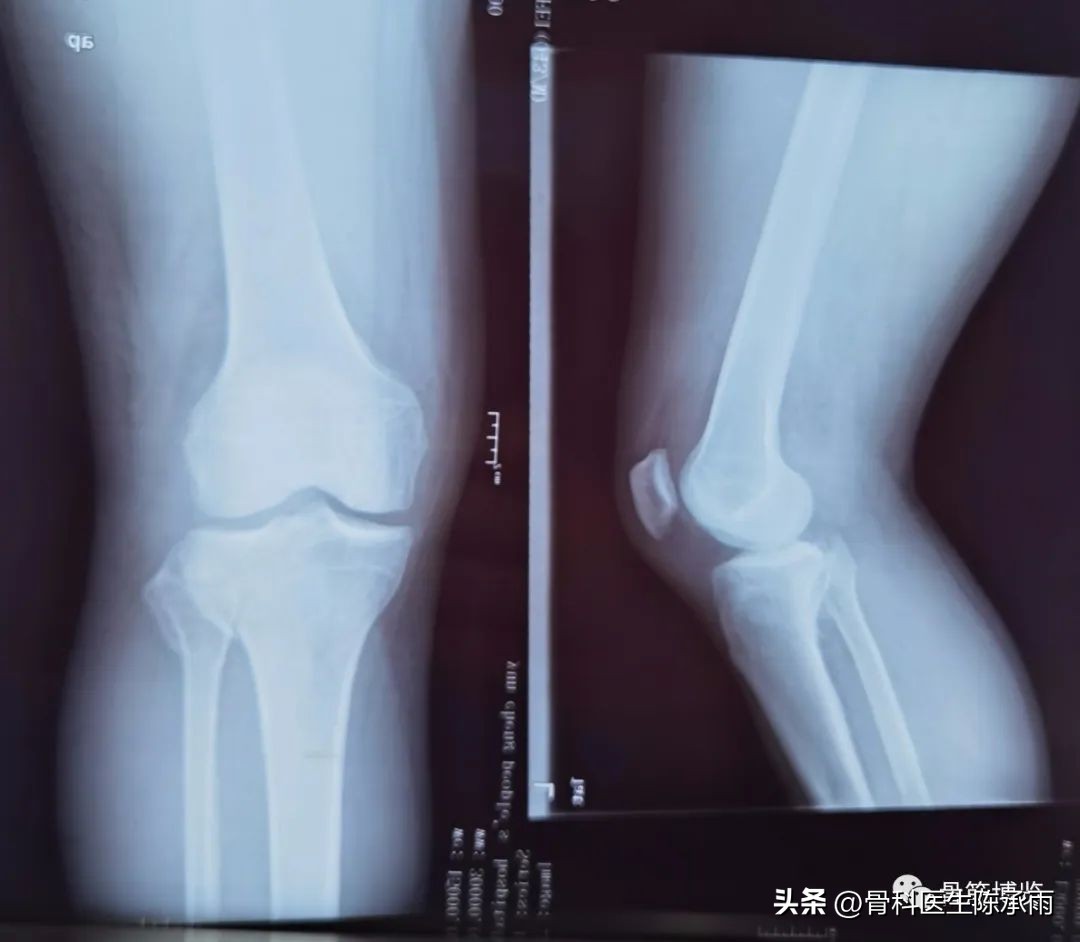

近段时间的胫骨平台骨折,没来得及详细整理

胫骨平台骨折的分型比较多,我们临床上常用的就是Schatzker分型和AO骨折的分型,还有骨折脱位的Hohi-Moore分型,这是我们常用的三个分型。

Schatzker分型来讲它一共分为六型:

一型 劈裂,

二型 劈裂塌陷,

三型 外髁的一个单纯塌陷,

四型 内髁的骨折,

五型 双髁的骨折,

六型 双髁伴干骺端的骨折,